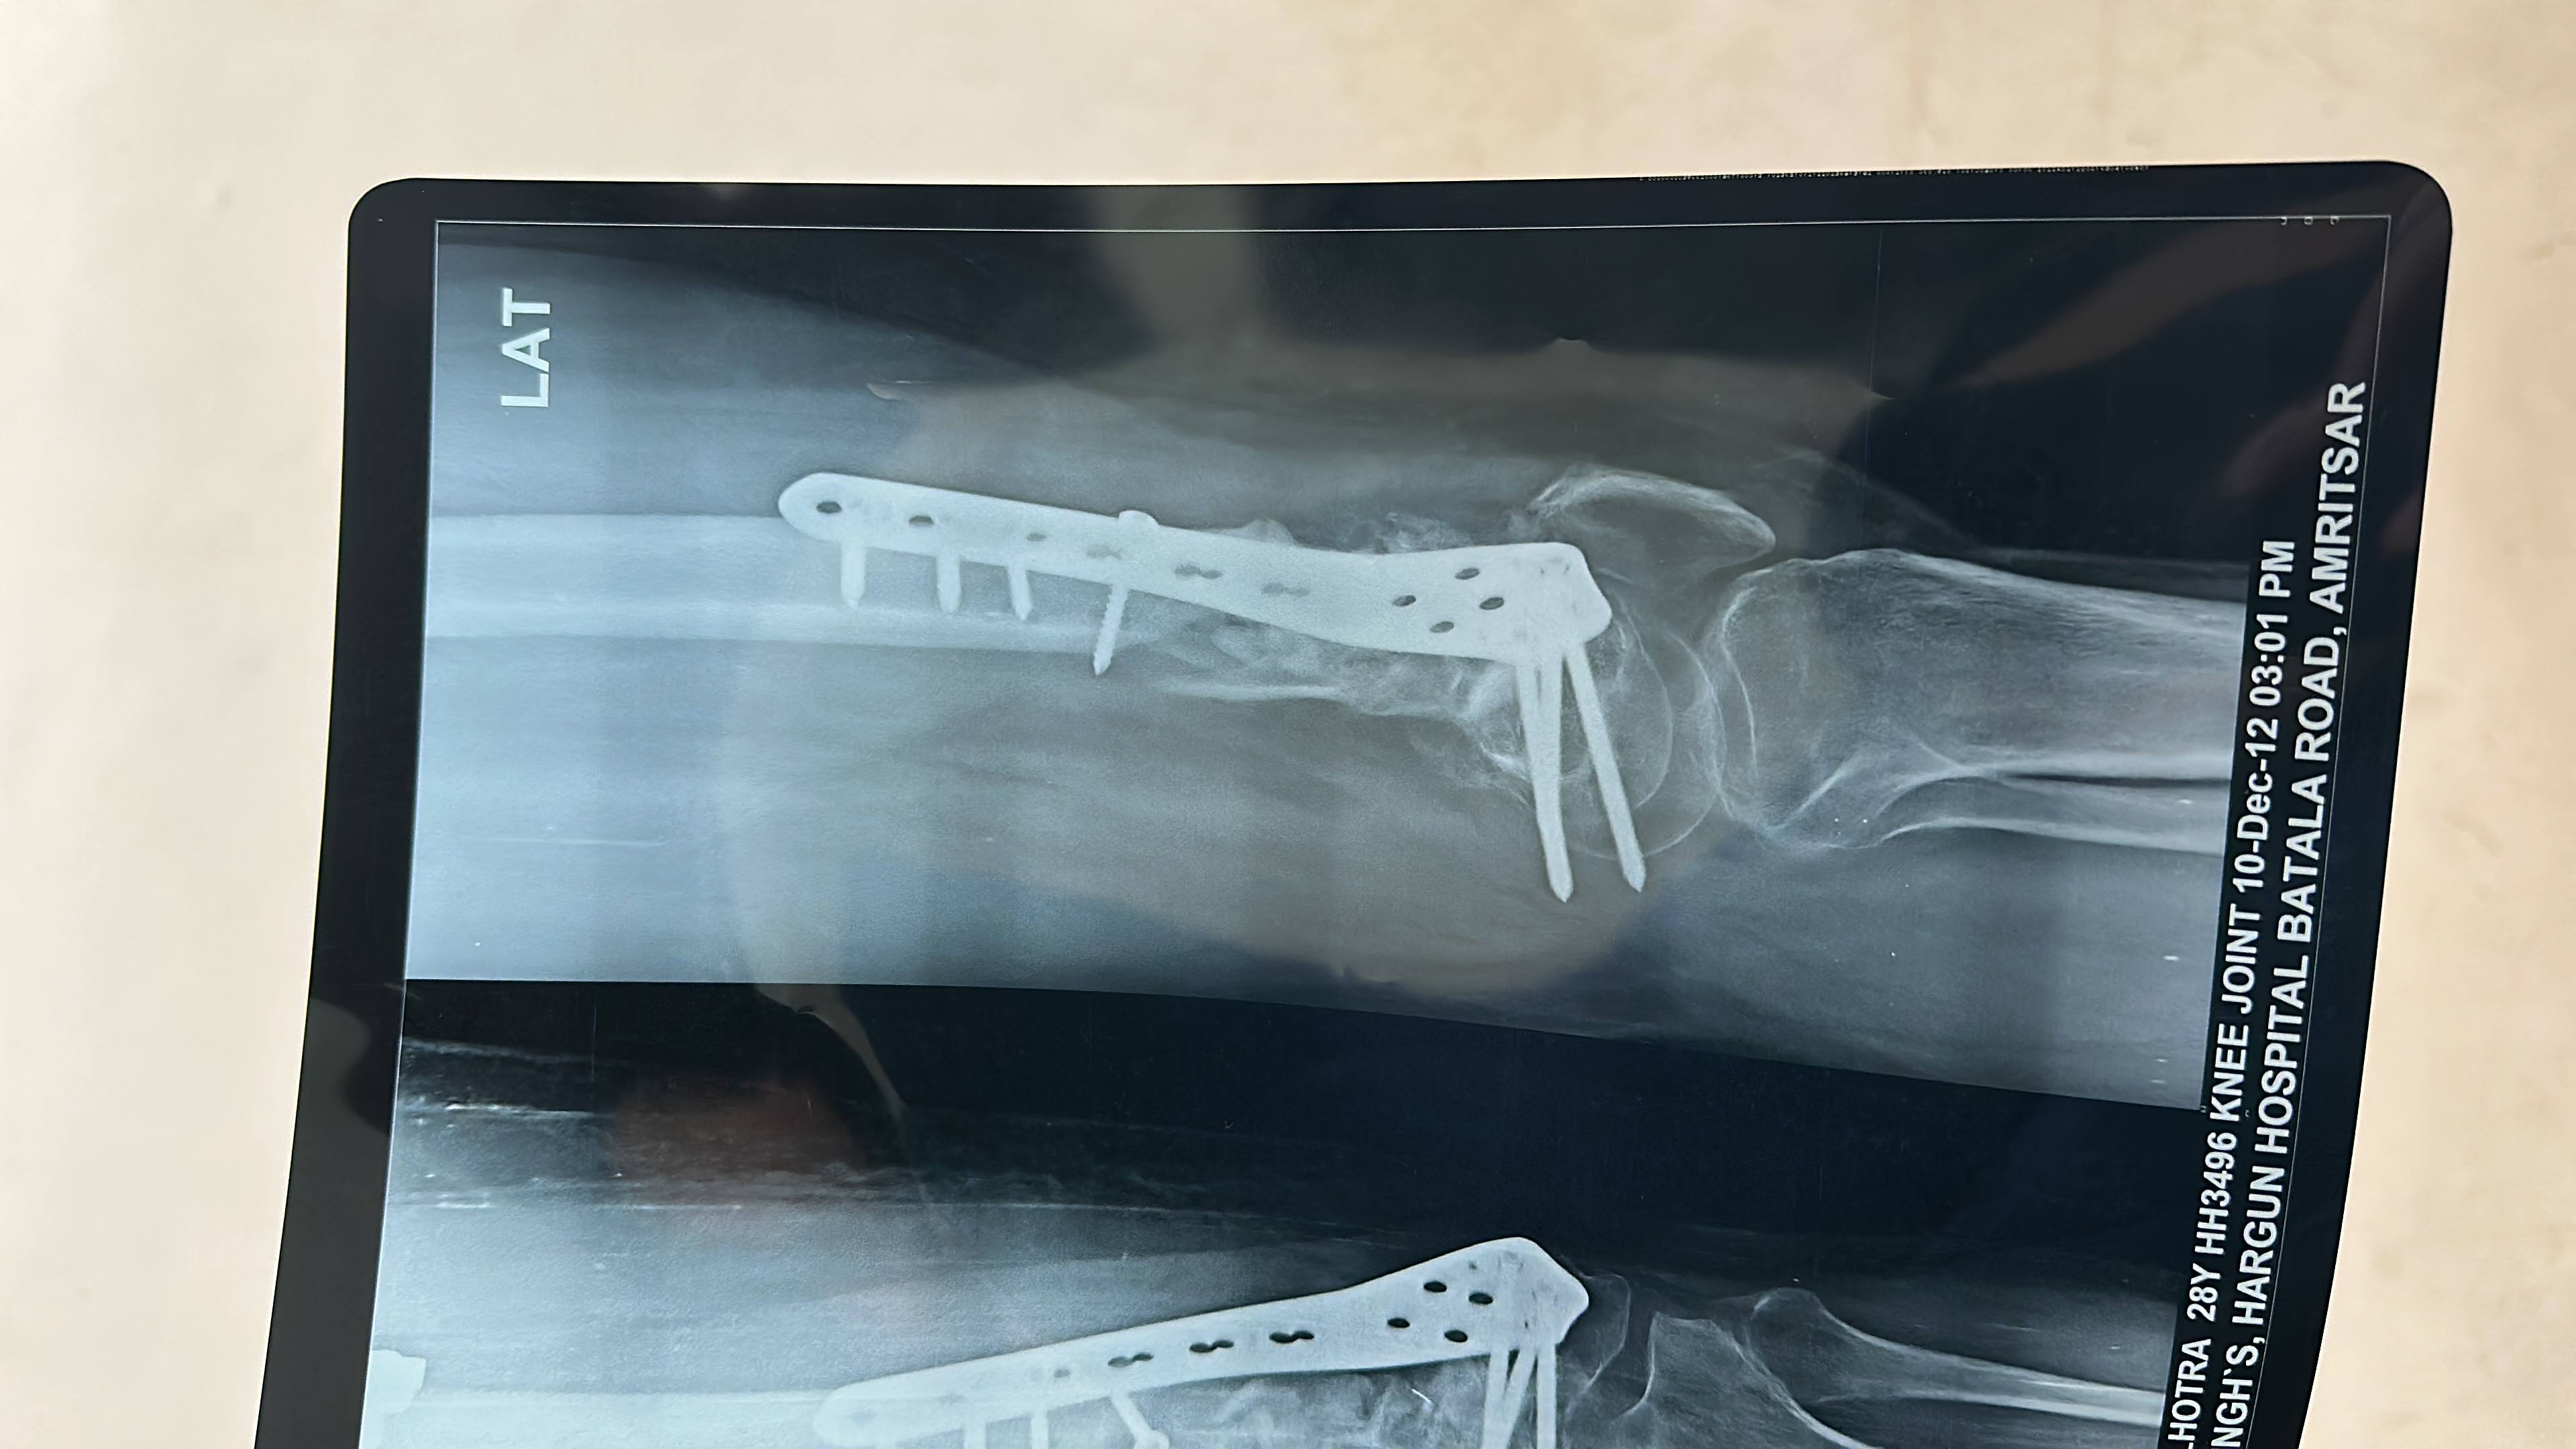

BABLU Malhotra

Bobby Malhotra

Knee bending nai horaha 2 months phle bone graft bhi hua hai kyse hoga sir bending?????